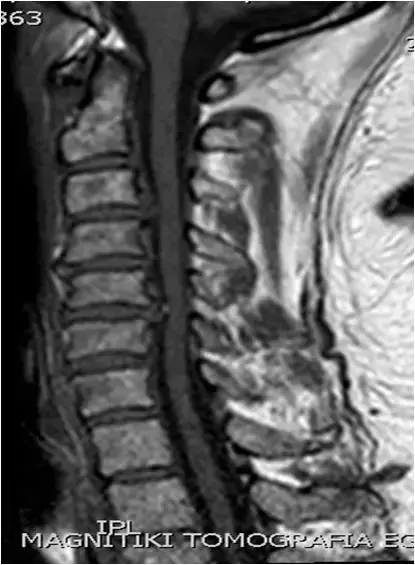

图36:矢状位 T1 TSE图像。 中线部分。生理曲度变直,多个椎间盘向后突出。

图37、矢状位T2 TSE图像。 中线部分。 与图像37相同的患者。颈椎的拉伸。 鉴定出多级椎间盘病变(C3-C4,C4-C5,C5-C6)。